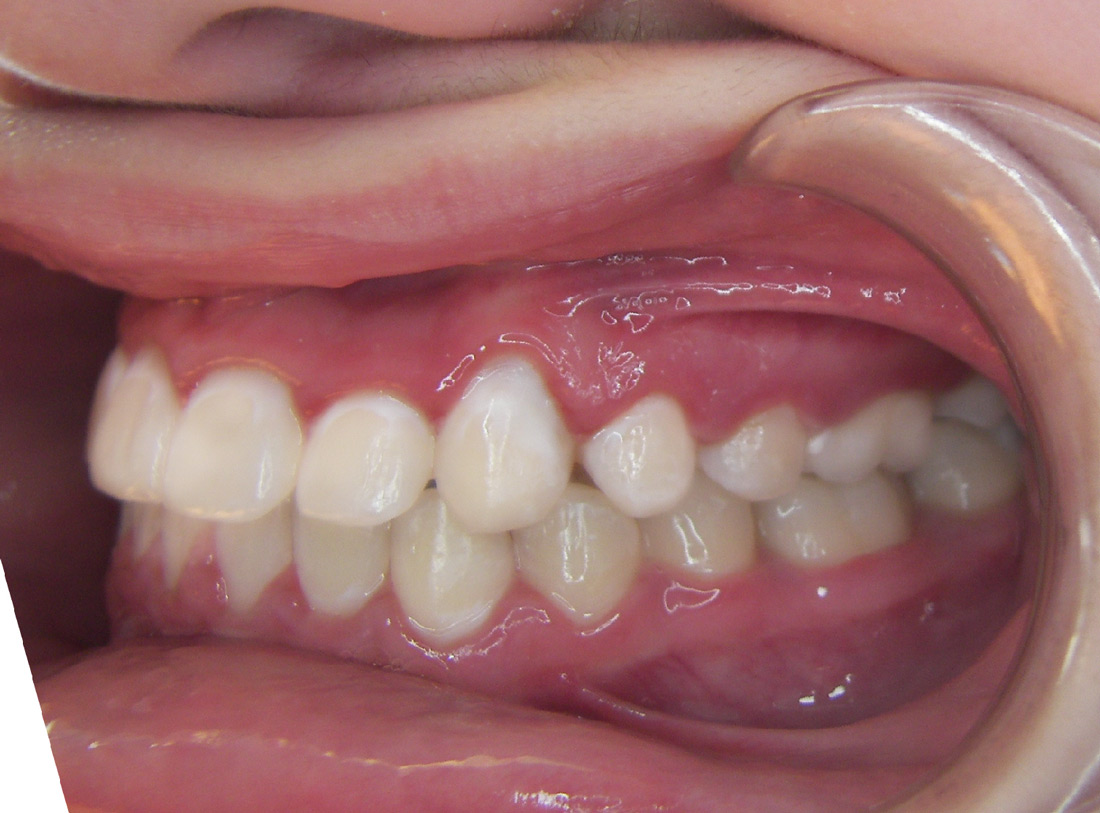

Case Studies

We’re proud of our patients’ new smiles, and most times, they’re even more proud to show them off. You’ll be ready for your close-up, too, once you visit the friendly experts at LB Orthodontics. Click here to see our smile gallery.